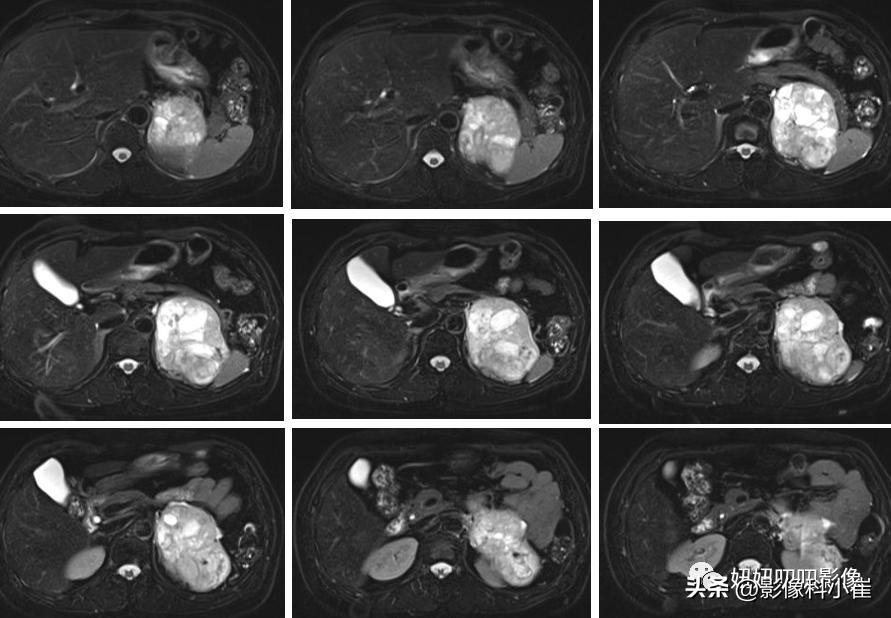

影像描述:

左侧肾上腺区见一团块状等长T1 等长T2 混杂信号,边界尚清,DWI示部分弥散受限,T1 反相位信号未见明显减低,最大截面约9.7X7.0X71,其内见点状短T2 信号,增强扫描呈明显渐进性不均匀强化,邻近组织受压。右侧肾上腺形态、信号未见异常,增强后未见异常强化。双肾见小圆形长T1长T2 信号,边界尚清,增强扫描未见明显异常强化。腹腔及腹膜后未见明显增大淋巴结。腹腔内未见明显液体信号灶。

见点状钙化,强化明显,T2亮,血压也升高,第一感觉还是嗜铬细胞瘤。

病理是肾上腺皮质腺瘤。

别问,问就是忘了也不会,说明腺瘤还真啥样子都行呢,所以到底哪里不像嗜铬细胞瘤呢?